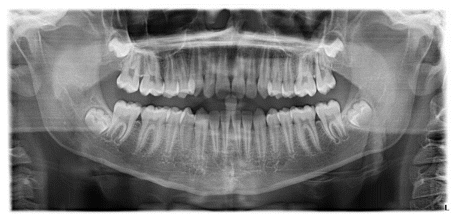

The patient was a young female presenting with a Class III dento-skeletal malocclusion, which was treated using the AMCOP® TC appliance. A comprehensive diagnostic protocol was carried out both before and after treatment, including orthopantomography (Figure 2–3), postero-anterior teleradiography (Figures 4, 5), latero-lateral cephalometric radiography (Figures 6, 7), cephalometric analysis (Tables 1, 2), as well as extraoral (Figures 8, 9) and intraoral photographs (Figures 10, 11). The extraoral examination revealed an edge-to-edge incisal relationship and the presence of a midline diastema. Pre-treatment cephalometric analysis (Deltadent® Lana, Bolzano, Italy) confirmed the diagnosis of a skeletal Class III malocclusion. The treatment plan involved the use of the AMCOP® TC appliance. The patient was instructed to wear the device for two hours in the afternoon and throughout the night for the first six months, followed by nighttime use only for an additional six months. Upon completion of the treatment, the patient achieved a Class I occlusion, with correction of both overjet and overbite. Additionally, the device facilitated tongue re-education and contributed to the postural realignment of the first cervical vertebra.